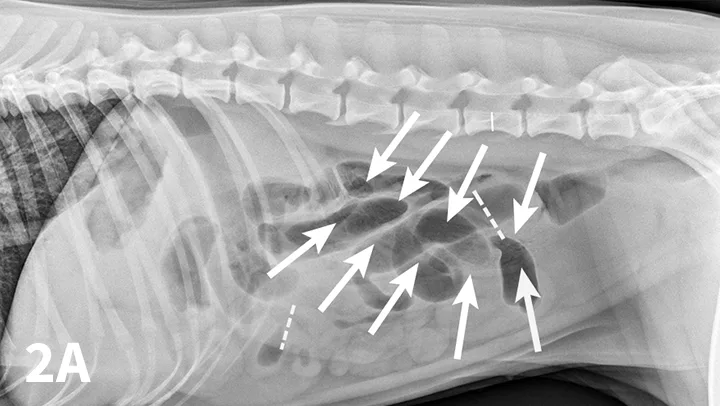

Radiographic features of small intestinal mechanical obstruction depend on its completeness, location, and duration.2 Whereas metallic FBs or those with mineral content are easily recognized within the GI lumen (Figure 1), nonmineralized, nonmetallic objects (eg, cloth) within the GI tract are more difficult to identify (Figure 2). Some may be recognized by their geometric shape. The most consistent sign of mechanical obstruction is variable dilation of intestinal loops proximal (orad) to the obstruction (described as a mixed population of small intestine; Figure 2). Determination of small intestinal diameter can be made by comparing it to the L5 vertebral body height in dogs.3 Values greater than 1.6 are suggestive of obstruction (Figure 2A). In cats, a ratio of the maximum small intestinal diameter to vertebral end plate height of L2 greater than 4 indicates a high likelihood of intestinal obstruction.4

FIGURE 2

Right lateral (A) and VD (B) abdominal radiographs of a Labrador retriever with an obstructive ileus. A FB (sock) is present within a dilated small intestinal loop in the right caudoventral abdomen (arrows). The dashed lines outline a fluid-filled loop measuring 2.7 cm and a gas-filled loop measuring 2.4 cm, compared to the height of L5 (Asolid line, 1.1 cm);  the resulting ratios of 2.4 and 2.2, respectively, are much greater than the upper limit of 1.6 for normal small intestine to L5 height ratio. Several stacked gas-filled loops of small intestine are present in the left midabdomen (B).